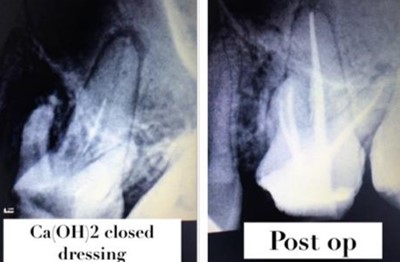

PRE - OP POST - OP